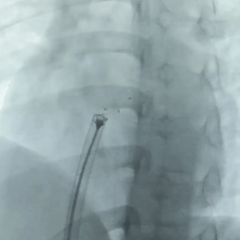

术中复测及封堵策略:术中超声复测缺损大小约19.1×17.9mm,经综合评估后,决定经股路径介入,选择BDASD-I 28可降解封堵器、16F可降解封堵器介入输送系统进行封堵,手术全程通过超声+DSA引导进行。

左盘展开

DSA下,左盘3个及腰部1个mark点推出,左盘展开,牵拉成型线,辅助左盘成型

后撤钢缆和鞘管,使左盘贴靠房间隔

右盘展开

固定钢缆不动 ,后撤鞘管展开右盘,钢缆及鞘管轻轻前推,使右盘贴靠于房间隔上

超声下确定封堵器左右两盘骑跨在房间隔两侧

锁定前牵拉试验

仅封堵器右盘随着牵拉发生形变

成型锁定

鞘管抵住封堵器后,前顶钢缆,随后固定钢缆和鞘管,向后牵拉成型线进行锁定

锁定后牵拉试验

DSA下,封堵器5个mark点随着牵拉整体移动

超声下,封堵器结构稳定无散开,判断锁定成功

释放封堵器

前抵鞘管,逆时针旋拧钢缆,封堵器释放,DSA下,5个mark点相对位置不变

释放后观察

封堵器位置正确、夹持稳定、形态良好、无残余分流,封堵手术成功